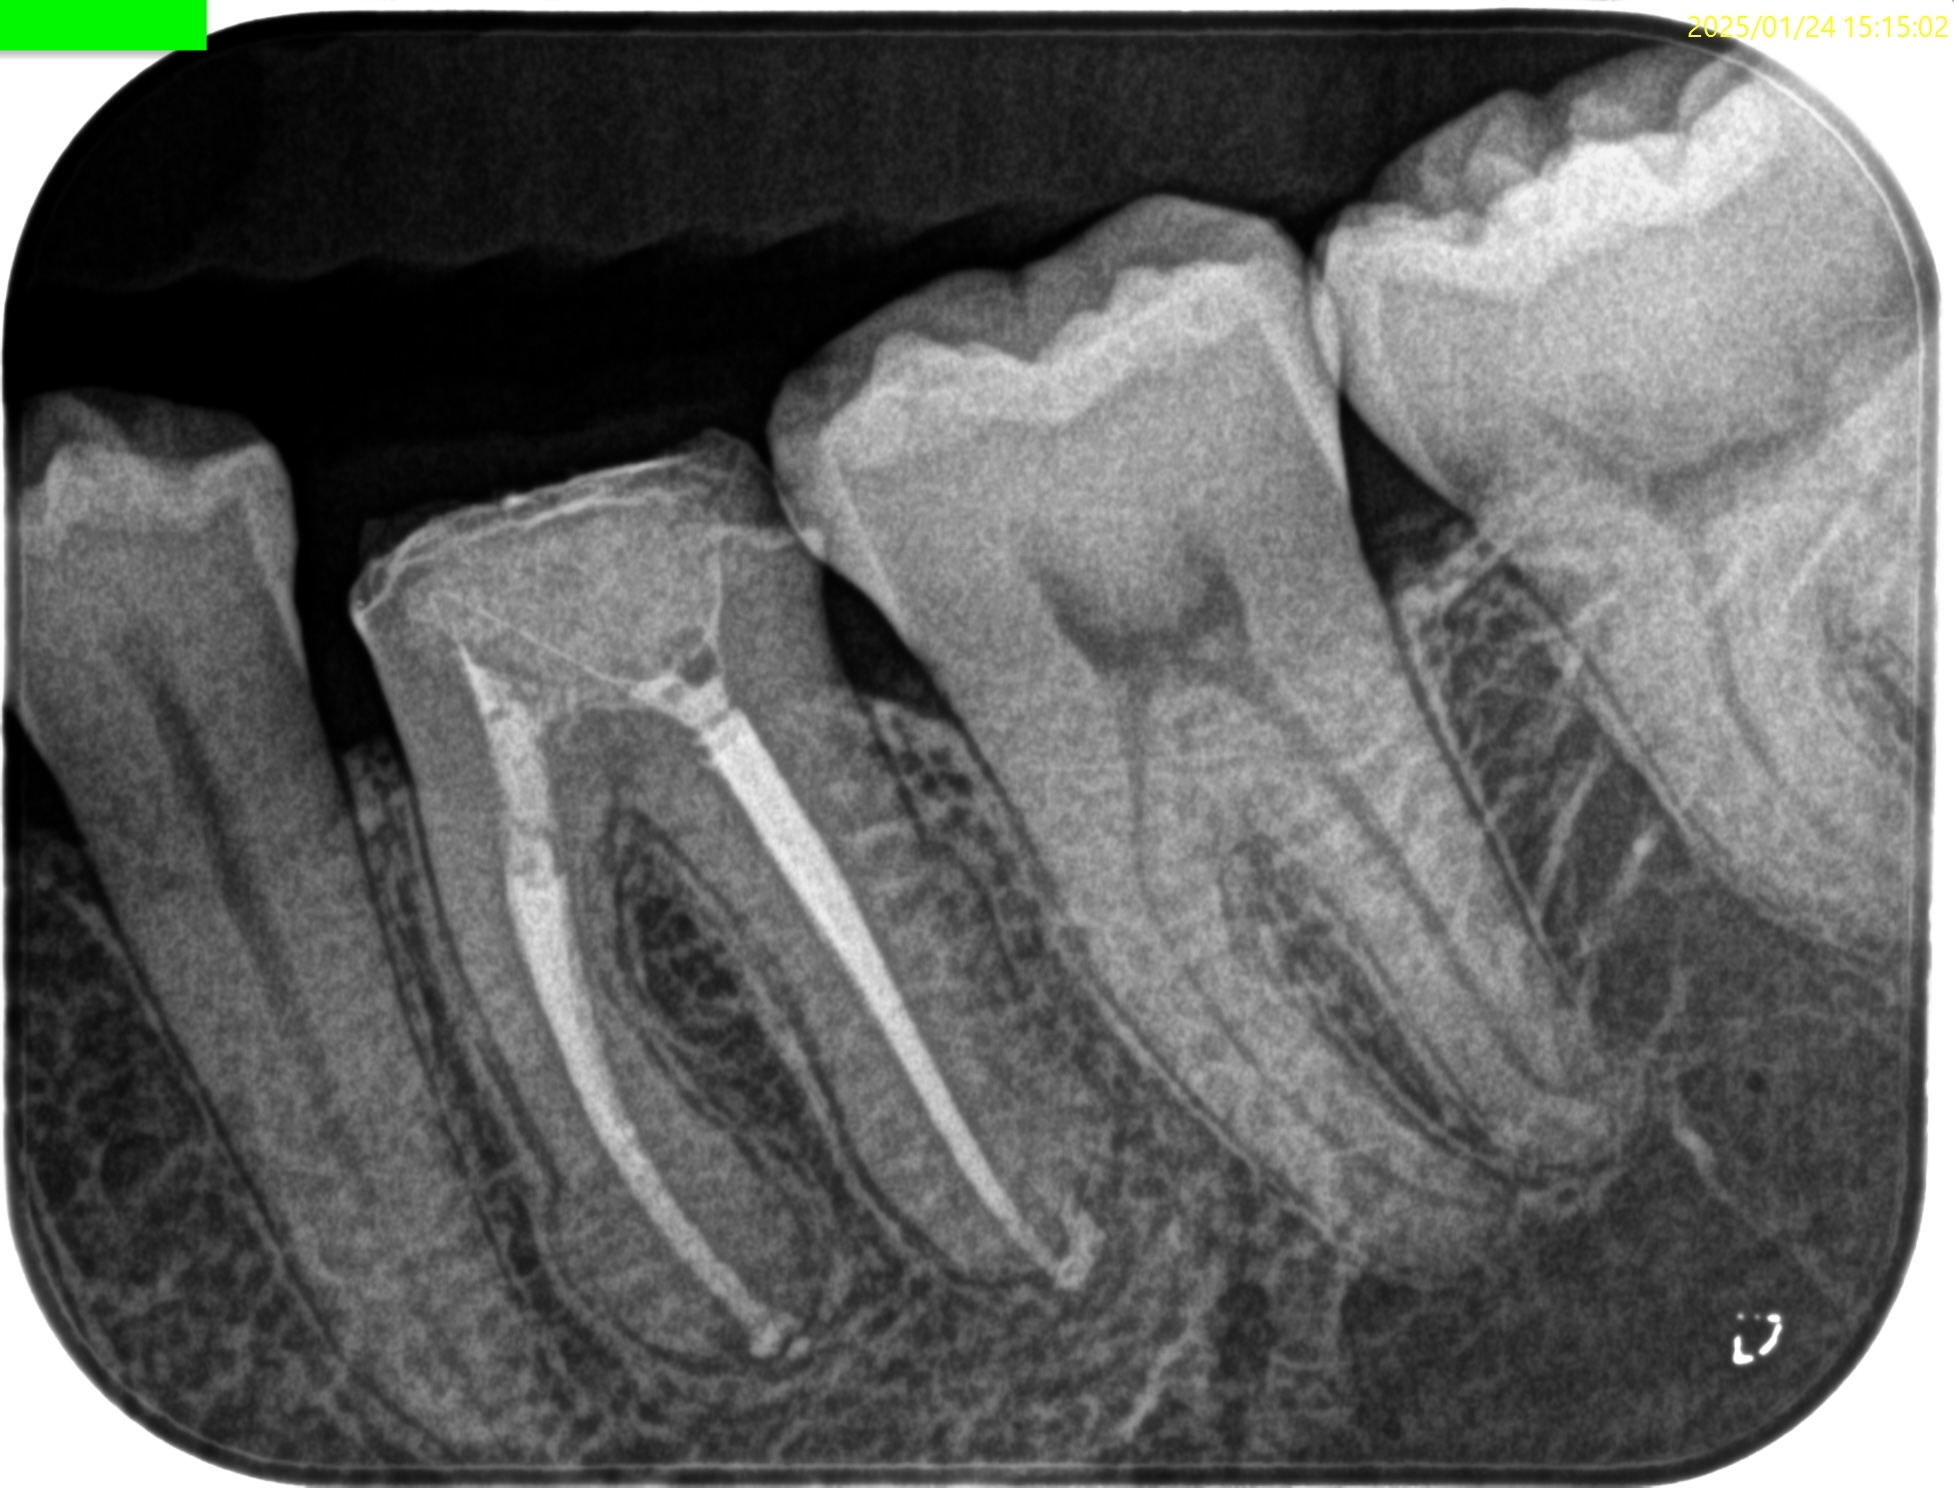

昨日の記事の経過観察。

治療から1年が経過していた。

臨床症状は1年経過してもないそうだ。

画像的にはどうだろうか?

初診時と比較した。

大きく問題が解決していることがわかるだろう。

ファイルが折れたMBも、

Overextensionした?ML,Dも、

根尖病変が消失している。

これはひとえに、

ルールを遵守した歯内療法の成果であるといえよう。

経過観察もこの日で終診とさせていただいた。